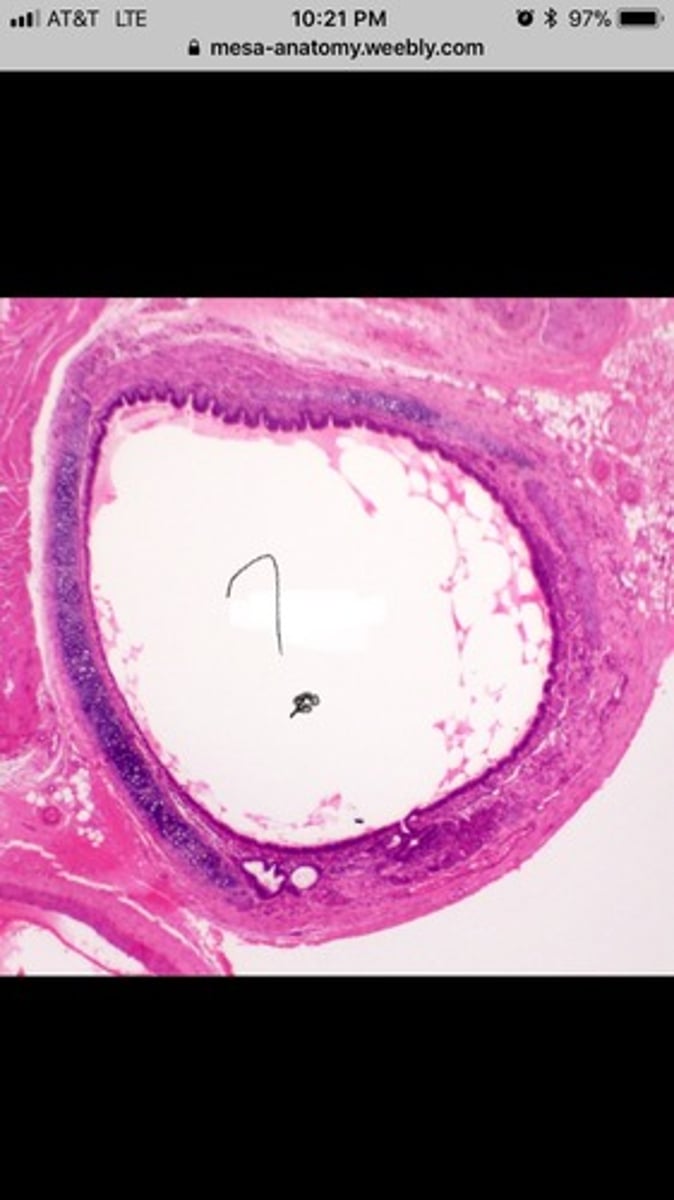

trachea: histology

layers- mucosa- ciliated pseudostratified columnar epithelium with goblet cells (mucus producing cells); mucus sticks to dirt/dust particles and is swept out of respiratory tract by cilia

submucosa

cartilage- hyaline cartilage

adventitia- external layer

trachea histology ex.